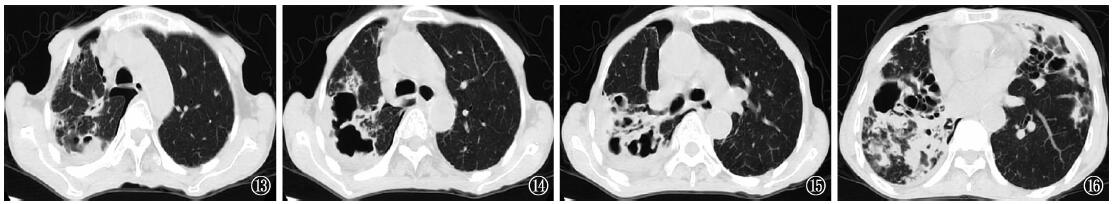

目的: 报道1例亚洲分枝杆菌肺病患者临床诊治过程,并结合文献分析该病临床特征、影像特点及预后。方法: 以1971年1月至2019年9月为检索时间,分别从PubMed数据库中以“Mycobacterium asiaticum”为检索词检索到27篇相关文献,其中仅有7例为亚洲分枝杆菌肺病患者报道;而以“亚洲分枝杆菌,肺病”为检索词在万方数据库和中国知网数据库中均未检索到相关文献。总结本例患者特征并进行入选患者文献复习。结果: 本例亚洲分枝杆菌肺病患者为中老年女性,且合并结构性肺病,以咳嗽、咳痰为主诉,以支气管扩张、空洞为主要影像表现,痰液及肺泡灌洗液抗酸杆菌涂片及快速分枝杆菌培养均为阳性,DNA微阵列芯片法菌种鉴定均为结核分枝杆菌复合群,药物敏感性试验(液体法)提示对利福平、异烟肼、左氧氟沙星、贝达喹啉均耐药,血γ-干扰素释放试验、痰液及肺泡灌洗液TB-RNA和TB-DNA、探针熔解曲线法检测结核分枝杆菌对利福平和异烟肼耐药均为阴性,经肺泡灌洗液多种病原体靶向测序(tNGS)提示为亚洲分枝杆菌而临床确诊。抗非结核分枝杆菌药物治疗8个月后,患者呼吸道症状缓解、病灶好转,痰液及肺泡灌洗液分枝杆菌培养阴转,治疗有效。另7例报道患者中,合并结构性肺病4例,合并肿瘤1例(未启动治疗),5例肺部病灶以结节和空洞形成为主;治疗方案存在差异,其中3例接受1年以上治疗后实现临床治愈,2例临床症状及影像学有好转(包括1例实现细菌学阴转),1例复发。结论: 亚洲分枝杆菌肺病相关报道较少,临床表现不典型,易误诊,对抗酸杆菌涂片及分枝杆菌培养阳性且菌种鉴定提示为结核分枝杆菌复合群但TB-RNA和TB-DNA阴性的患者,应注意排除非结核分枝杆菌肺病,tNGS检测有助于临床诊断,值得临床医生重视。

Objective: To report the clinical diagnosis and treatment of a patient with Mycobacterium asiaticum pulmonary disease, and to analyze the clinical features, imaging characteristics, and prognosis of the disease in conjunction with a review of the literature. Methods: From January 1971 to September 2019, we searched, 27 relevant literatures were retrieved from PubMed database with “Mycobacterium asiaticum” as the searching term, of which only 7 cases were Mycobacterium asiaticum pulmonary disease cases. “Mycobacterium asiaticum, pulmonary disease” as the search term, no relevant literature was found in both Wanfang database and CNKI database. We summarized the characteristics of our patient and reviewed the literature of the selected cases. Results: Our patient with Mycobacterium asiaticum pulmonary disease was a middle-aged woman with structural pulmonary disease, with cough and sputum as the main complaints, bronchial dilatation and cavitation as the main image manifestations. Sputum and bronchoalveolar lavage fluid were positive for acid-fast staining and mycobacterial culture. DNA microarray chip method identified all as Mycobacterium tuberculosis complex, and they were resistant to rifampicin, isoniazid, levofloxacin, and bedaquiline. However, negative IGRA, and negative sputum/bronchoalveolar lavage fluid (BALF) TB-RNA and TB-DNA, and negative Mycobacterium tuberculosis molecular drug resistance detection (INH, RFP; probe melting curve method). BALF tNGS results suggested a clinical diagnosis of Mycobacterium asiaticum pulmonary disease. After treatment with anti-non-tuberculous mycobacterium drugs, the patient’s respiratory symptoms were relieved after 8 months of treatment, the lesion improved, and mycobacterial culture of sputum and BALF turned negative, indicating effective treatment. In the other 7 cases, there were 4 cases complicated with structural lung disease and 1 case complicated with tumor (no treatment was started). The lung lesions were mainly nodules and cavities formed, and there were differences in treatment plans. Finally, 3 cases achieved clinical cure after more than 1 year of treatment, 2 cases showed improvement in clinical symptoms and imaging (including 1 case achieved bacteriological negative conversion), and 1 case relapsed. Conclusion: Reports on Mycobacterium asiaticum pulmonary disease are scarce, and the clinical manifestations are atypical and easily misdiagnosed. In patients with positive acid-fast staining and mycobacterial culture and mycobacterial identification suggestive of the Mycobacterium tuberculosis complex but negative for TB-RNA and TB-DNA, it is important to consider non-tuberculous mycobacterial pulmonary disease. The tNGS test aids in clinical diagnosis and should be emphasized by clinicians.